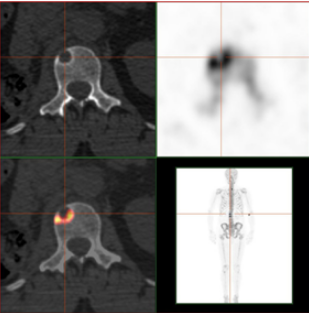

除随访外,如果患者感觉周身不适,例如某一部位感觉疼痛,应该及时寻求专科医生的帮助,进行骨扫描,以及X线、CT、核磁等影像学检查,来判断是否发生了骨转移。PET进行骨转移癌诊断可能会更全面、准确。